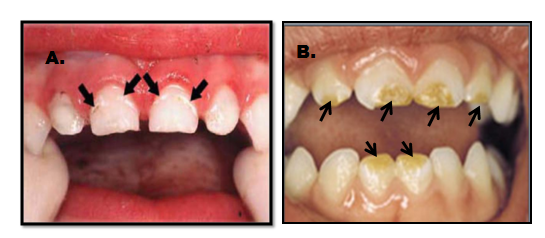

Prema spoljašnjem izgledu oštećenja gleđi nepravilnosti mogu da budu samo u obliku promene boje(bela, žućkasta) sto se naziva stručno HIPOMATURACIJA(bele mrlje-videti na kraju teksta), ili pravih defekata nepravilnog oblika što se naziva HIPOPLAZIJA.(slika 1.)

Slika 1. Oblici razvojinih nepravilnosti gleđi: a) HIPOMATURACIJA (desno) b) HIPOPLAZIJA (levo)

Razvojna oštećenja su posledica stvaranja manje kvalitetne gleđi ili potpunog nedostataka gleđi na pojedinim mestima. Ponekada, po nicanju zuba, takva gleđ je samo promenjenog izgleda(hipomaturacija), ali je slabije mehaničke otpornosti i usled pritisaka dolazi do njegnog pucanja i prelaska u defekt(hipoplaziju).